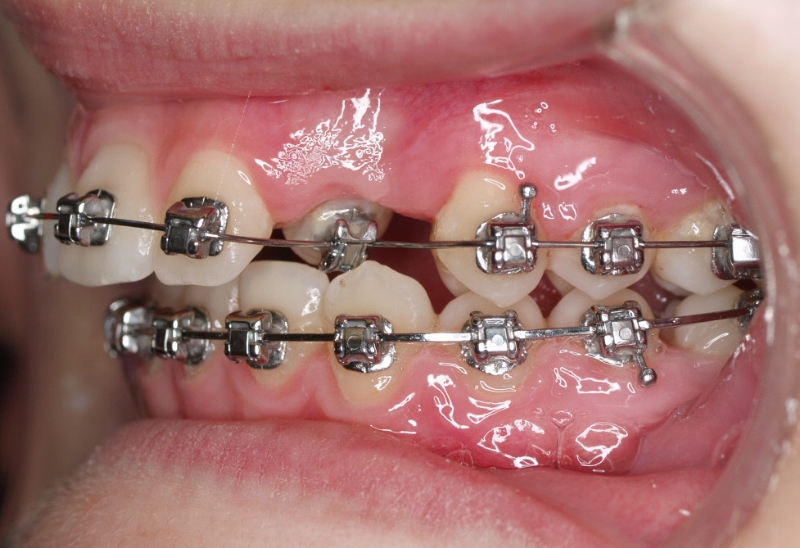

La paciente O.O. acude a nuestra consulta por:

– Canino 13 e incisivo lateral 42 en posición ectópica.

– Canino 23 incluido.

Con lo que decide realizarse un tratamiento de ortodoncia de duración de 24 meses con brackets damon Q.